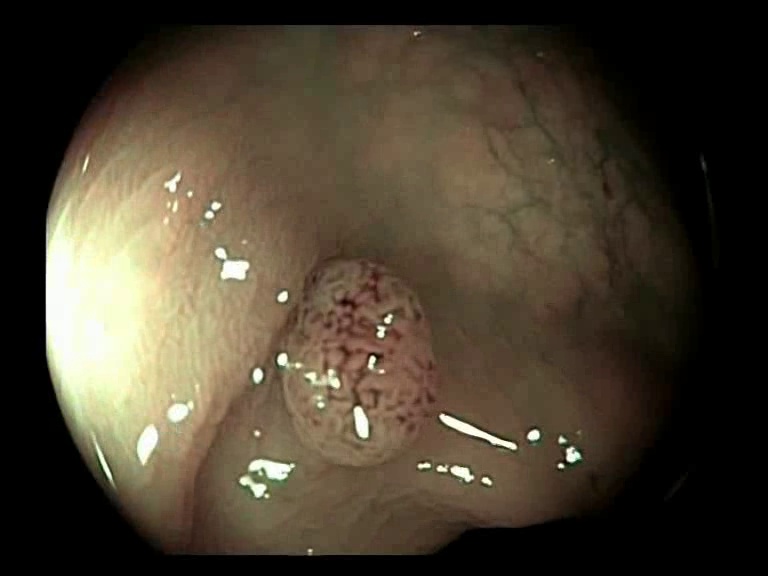

Figure 3: Key-frames obtained by our method and their corresponding depth maps. The polyp is visible from different viewing angles in these selected frames.

The selected key-frames are finally used to reconstruct the 3D surface of the polyp. We have used Facebook’s 3D image GUI to view the reconstructed polyp surface, the link to the video is shown here: https://youtu.be/PJKfk0Mqu2I\href https://youtu.be/PJKfk0Mqu2I. 3D visualization of a polyp helps in surgeries involving the removal of the polyp from its root. This gives better visualization of polyps for diagnosis. Fig. 3 shows some of the results of key-frame extraction and the corresponding depth maps. No publicly available datasets or methods using them that predict depth maps from endoscopic frames exist. Thus, a comparison between different methods for predicting depth from endoscopic images couldn’t be performed.